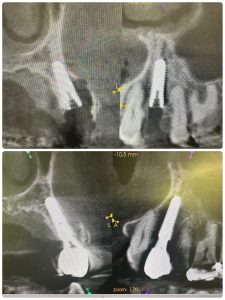

次のお方はオペ後6w、ISQも80台、仮歯まで